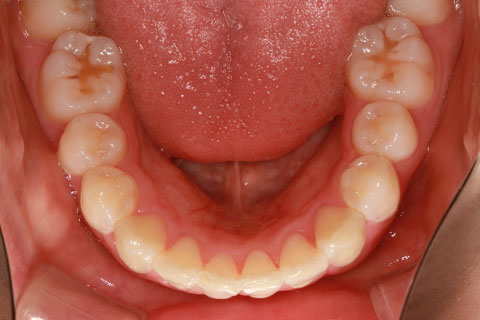

ハーフリンガル矯正3:上の歯のみ舌側矯正で治療(矯正期間24ヶ月)

治療前

治療中(開始直後)

治療中(開始半年後)

治療後

- 年齢・性別

- 25歳女性

- 治療期間

- 2年0ヶ月

- 抜歯

- 上下4番抜歯

- 治療費

- 110万円

- 治療内容

- 表側矯正と比較して、力学的な操作性が複雑なため、ボーイングエフェクトを起こしやすい。